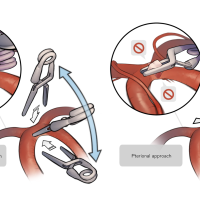

術後イラストシリーズ

OPExPARKコンテンツ・脳神経外科速報寄稿シリーズ